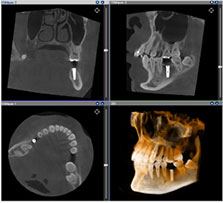

三次元CTにて精密検査

最新の高性能3次元CT「AUGE SOLIO」を導入しております。 従来の2次元の歯科用レントゲンとは違い、3次元CTは、お口の環境や歯根の形状、骨の状態まで、お口の中をより詳細に正確な検査することができ、しっかりとした治療計画を立てることが可能です。放射線量は10分の1以下で、安心で安全な治療のご提供を実現しています。

使用するインプラントの種類や本数、上部構造の材質、骨造成などの先進的な治療の必要性の有無などによって個人毎に費用が異なります。インプラントの初回カウンセリング費用は無料となっておりますので、お気軽にご相談ください。 当院では、CT撮影などの精密な検査の後に事前にコンピューター上でシミュレーションを行い、患者さまの口腔内の状況やご希望に合わせて適切な治療計画をご提案させていただいております。